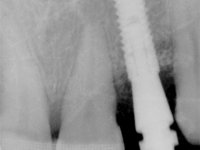

Female patient, 47 years old non-smoker. Tooth 1.3 with endodontic treatment and a cast post and core, rehabilitated with a provisional crown. The two upper lateral incisors are conoid and of small dimension. Tooth 2.2 presents mobility, in agreement with a significant bone reabsorption between teeth 2.1 and 2.3. The two central incisors are separated by a 3 mm diastema and tooth 2.3 presents a crossed occlusion with the opposing tooth. There is also an absence of some posterior teeth and reasonable oral hygiene. In the second intervention performed 8 years later, it was verified that the upper central incisors were chromatically darker and had a longitudinal groove in the enamel which, being pigmented, aesthetically compromised the smile. The work performed in the first phase of the treatment was competent, aesthetically and functionally. Finally, one year after the last intervention, the patient complained of a fracture on the veneer placed on tooth 2.1, probably as a result of being in contact with the abutment of the implant. The rigidity of implant ankylosis may have been the cause of this fracture. I have observed other instances of this type of fracture in identical clinical situations. The veneer of tooth 1.2 was aesthetically compromised and the dental structure itself had small caries and, therefore, its replacement would be recommended.

• Orthodontic treatment to close diastema between maxillary central incisor teeth and slow tooth traction 2.2.

• Placement of an implant at the tooth site 2.2. Rehabilitation of the implant with a coronary and gingival component abutment. in which the screw access hole was "camouflaged" with a feldspathic veneer.

Treatment began with re-preparation of the cast post and core, with the purpose of placing the cervical finishing lines with an intra-sulcular location and simultaneously making a suitable temporary crown. With a very simple orthodontic treatment, the diastema was closed between the upper central incisors, and this position was stabilized with a wire placed on the palatal surface of the central, functioning as containment. Later, a slow orthodontic traction of tooth 2.2 was attempted, in order to reduce, although very slightly, the vertical bone loss in this area. At the end of the traction, tooth 2.2 was extracted and the area was provisionally rehabilitated with a composite resin crown bonded to the adjacent teeth. A dental implant was placed in the area of tooth 2.2 and the temporary crown was again bonded to resin, provisionally rehabilitating the patient during osseointegration. In tooth 1.3 a gingivectomy with an electric scalpel was performed, with the intention of raising the cervical level of 1.3 achieving greater harmony with tooth 2.3. Stabilized soft tissues were impressed using the open tray technique with putty and light addition silicones. Collection of the color of both the dental component and soft tissues was done by the ceramist in the office. In the laboratory, the impressions were transferred to plaster and gave origin to work models that were properly analyzed. It was decided to assemble a metal-ceramic abutment screwed onto the implant. This abutment was cast with a noble alloy and subsequently coated with coronary and gingival ceramics. Due to the inclination of the implant, the screwing inevitably conditioned the exit of the screw hole through the vestibular surface. In order to conceal this situation, the design of the abutment has already been conceived with the intention of accommodating on the vestibular surface the bonding of a feldspathic veneer. This abutment was tested in the mouth and adjustments were made in the gingival ceramic component. Its adaptation to the soft tissues was done in a subtractive way, with a drill, as well as additive, adding resin composed of gingival tonality.